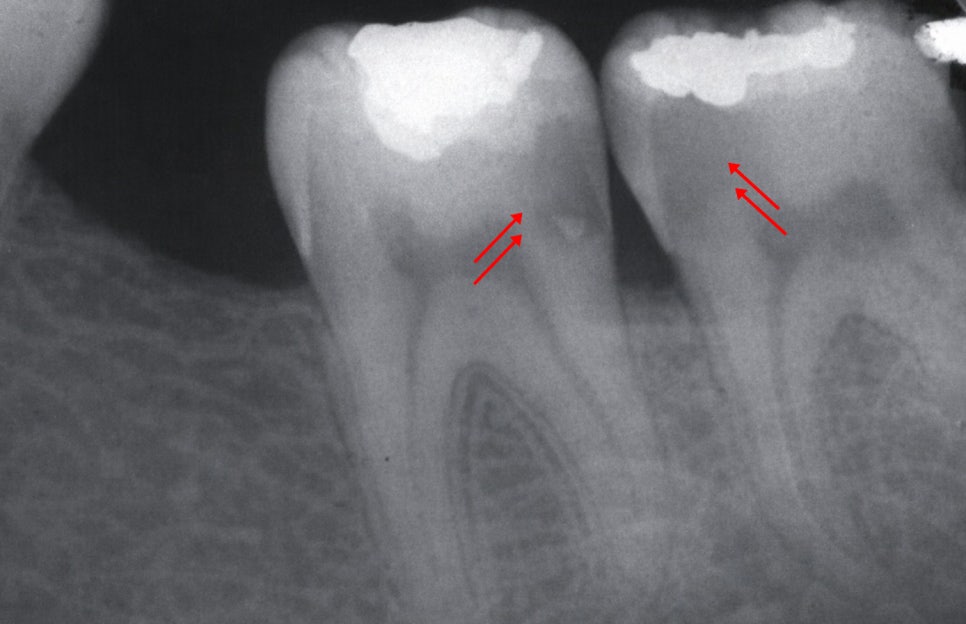

제일 대표적인 원인은 미세누출로

레진의 경우에는 재료 특성상

중합 수축이 발생해

레진이 굳는 과정에서 미세하게 수축하면서

변연 부위에 응력이 생기고

이로써 접착력이 약해질 수 있습니다.

또한 반복되는 저작력과 온도 변화도

수복물에 변화를 일으킬 수 있습니다.

2차 우식은 크라운 아래에서 진행되기 때문에

초기에는 겉으로 드러나는 변화가 없을 수 있습니다.

또한 보철 아래에서 발생한 충치는

외부 공기와 접촉하지 않기 때문에

비교적 습하고 밀폐된 환경에서

빠르게 진행될 수 있습니다.